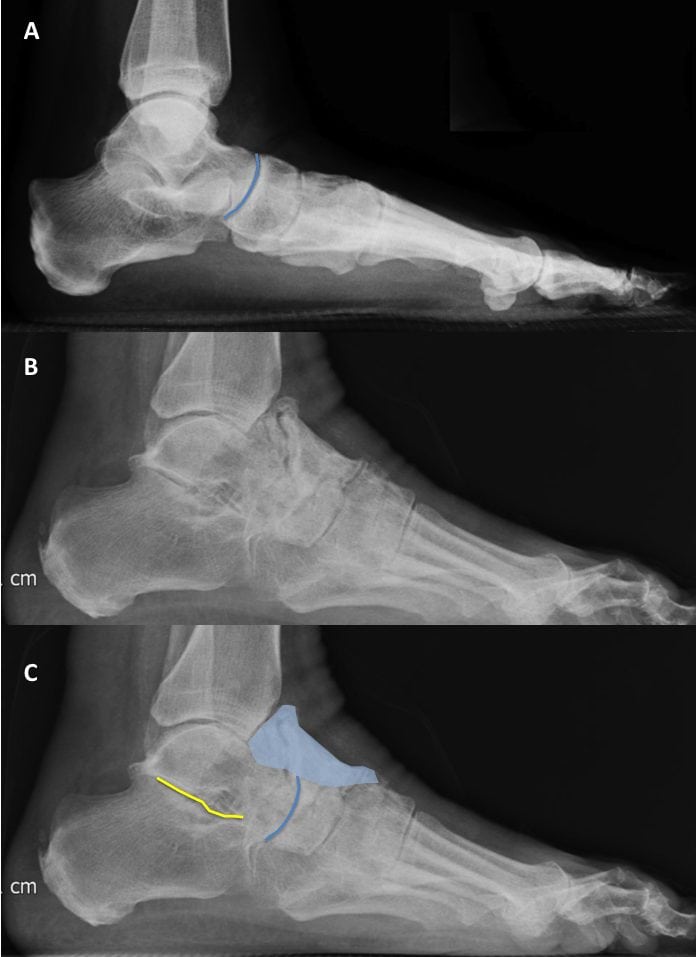

Остеоартроз 1 степени тяжести может клинически не проявляться. Изредка возникают слабые дискомфортные ощущения после физической нагрузки или переохлаждения, несколько ограничивается подвижность сустава. Проведение рентгенодиагностики позволяет выявить нечеткое сужение суставной щели, формирование единичных наростов на краях костных поверхностей.

На этой стадии ДОА появляется хруст. Щелчки, потрескивание сопровождают сгибание и разгибание голеностопа, отчетливо слышатся при ходьбе. Вместо незначительного дискомфорта теперь возникают боли. Они ноющие, тупые в состоянии покоя и давящие, сильные при движении. На рентгенографических изображениях хорошо заметны множественные остеофиты, признаки субхондрального остеосклероза в костных тканях. Суставная щель заметно сужена, поэтому подвижность голеностопа снижается.

Для остеоартроза высокой степени тяжести характерна выраженная деформация голеностопного сустава. Подвижность в нем сильно ограничена из-за отсутствия суставной щели. На 3 стадии ДОА образуются обширные остеофиты. При смещении костных наростов нередко травмируются мягкие ткани, провоцируя развитие воспалительного процесса. Также отмечается формирование субхондральных кист, суставных «мышей».